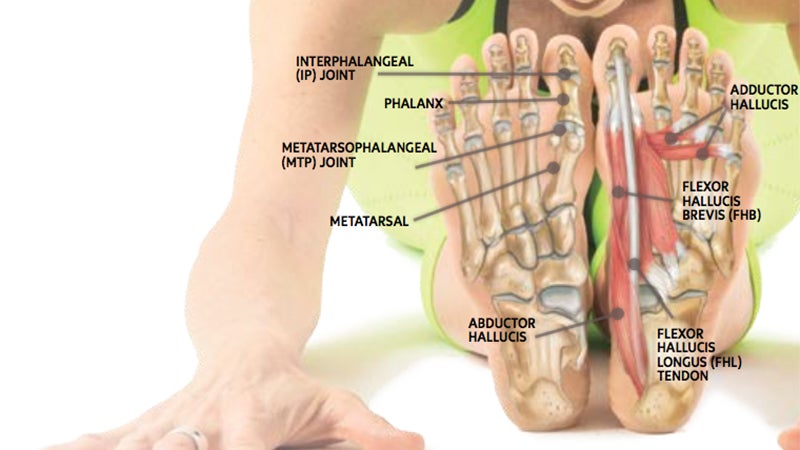

Anatomy 101 Strengthen Your Big Toes to Build Stability

Foot Ankle Tendons Anatomy Function Injuries